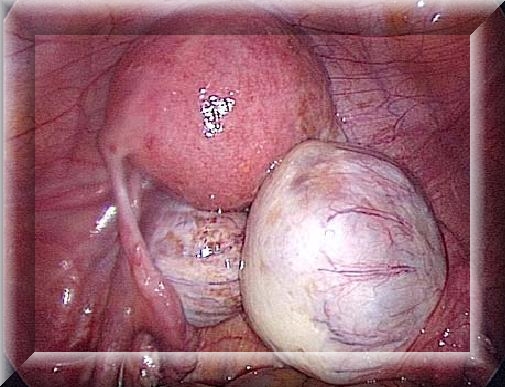

Рис.120. МРТ в режимах Т1 с контрастным усилением (а,б) и Т2 (в) выявляет гетерогенного строения опухоль больших размеров, практически полностью занимающую весь третий желудочек. Средний мозг грубо сдавлен и деформирован. КТ (г,д) после удаления опухоли затылочным транстенториальным доступом не выявляет се остатков. Под костным лоскутом в затылочной области определяется эпидуральная гематома.

Клинический пример